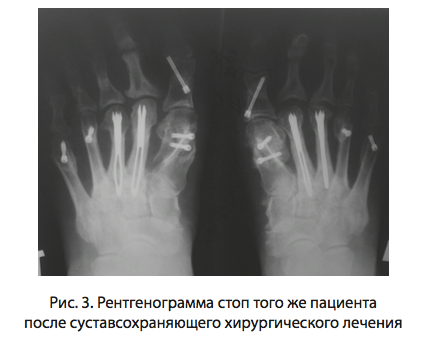

В зависимости от набора деформаций переднего отдела стоп проведены операции, диафизарная остеотомия Scarf первой плюсневой кости и операции Akin на основной фаланге 1 пальца для дополнения коррекции деформации первого луча стопы. Ригидные вывихи 2, 3, 4, 5 пальцев лечили сегментарной резекцией диафиза плюсневой кости с использованием метода Short Beam (фиг. 3) (SB) (Патент РФ No 2576790 от 10.02.2016).

Оценка рентгенограмм проводилась до и после оперативного вмешательства через 3, 12 и 24 месяцев, в стандартных проекциях. Обращали внимание на положение имплантата, костных фрагментов и наличие выраженности консолидации в области проведенной остеотомии. В послеоперационном периоде у всех пациентов проводили наблюдение, перевязки, инфузионная терапия. Иммобилизация не требовалась ввиду стабильного остеосинтеза SB и остеосинтеза самокомпримирующими канюлированными винтами. Ходьба в туфлях Барука с первых суток после операции до 5 недель. Ранняя нагрузка особенно важна в восстановлении функций стопы ввиду стимуляции активных зон и особенностей кровоснабжения нижней конечности (мышечная помпа) [2,3]. Для улучшения микроциркуляции в раннем послеоперационном периоде проводилась инфузионная терапия с применением антикоагулянтов, дезагрегантов.

Отдаленные результаты лечения оценены у 66 пациентов с сегментарной резекцией диафиза малого луча (фиг. 4) и в 58 случаях резекции головки плюсневой кости по Clayton-Ho man в срок от 12 до 24 месяцев по трем критериям Groulier. Данные критерии позволяют по 85 бальной системе объективно оценить степень деформации первого луча, состояние переднего одела и функциональную активность. Средний балл в основной группе до операции составил 25 баллов, через 12 месяцев – 63 балла и через 24 месяца – 74 балла. В группе сравнения исходный средний балл составлял 25, через 12 месяцев – 41 балл и через 24 месяца – 52 балла. Анализ результатов лечения по предлагаемой методике показал ее высокую эффективность (рисунок 1).